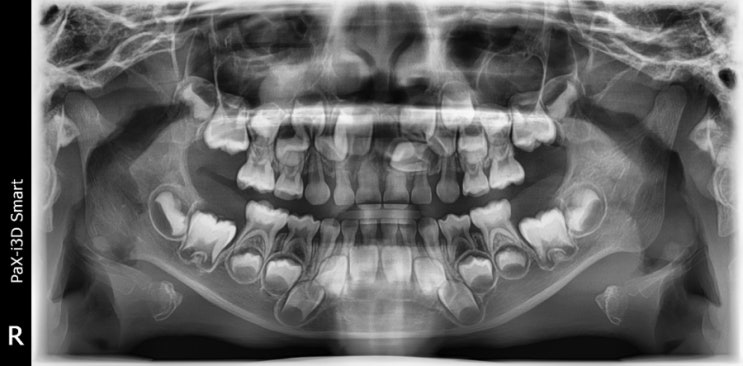

만5세 양산부산대병원에서 과잉치수술 후기

과잉치 프롤로그 때는 2022년, 아이가 태어난지 3년차 되던 해이다 구강검진차 갔던 어린이병원에서 충치가...